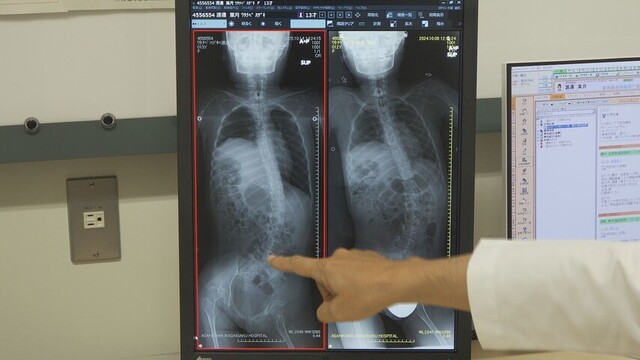

背骨を支える筋力が衰えたことで、側弯症を発症。症状が進行すると、消化器の病気や呼吸困難を引き起こすこともあるため、定期的にレントゲン検査を受けています。

医師:「去年と比べたら今年の方が、若干姿勢が良さそうです」。

医師:「骨もだんだん大人の骨になってくると、周りの支えがしっかりしてくるので、それで変形が目立たなくなってくることもある」。